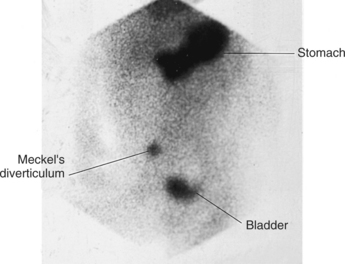

what is the investigation of choice for meckel’s diverticulum?

Tc 99 (Technetium-99m) pertechnetate scan

Tc-99 pertechnetate scan -?

Meckel’s Diverticulum